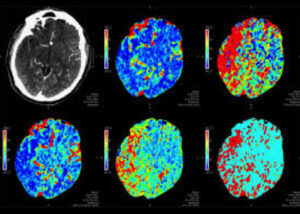

Thrombectomy after 6 hours of treatment.Many patients are treated with thrombectomy beyond the typical 6-hour time window. These patients are selected for treatment outside of the typical 6-hour window based on complex methods which typically include perfusion imaging (see color maps below). At ISC this year, we saw in the Trevo worldwide registry that fully 1/3 of thrombectomy patients received treatment in the > 6 hr time window and 1/5 of the thrombectomy patients in the Providence GWTG database were treated at greater than 6 hours. Patients treated in this delayed time window had worse discharge ranking scores but had no worse NIH stroke scale, length of stay. These data suggest that properly selected patients in the delayed time window derive almost as much benefit as patients treated in the early time window. Our research was presented as one of two studies detailing stroke transfer times and outcomes in data from 562 acute ischemic stroke patients with large vessel occlusions and is described in Clinical Neurology News.

Perfusion Imaging and Thrombectomy

Perfusion Imaging and ThrombectomyIn a pooled analysis of six thrombectomy trials, Dr. Bruce Campbell’s group showed that perfusion imaging combined with RAPID software strongly predicted outcome after thrombectomy.  Specifically, patients who had thrombectomy had worse outcomes if they showed larger area of core infarct on perfusion imaging prior to their treatment.  However, even for large volume infarcts at the time of thrombectomy, there was significant benefit to receiving the thrombectomy.